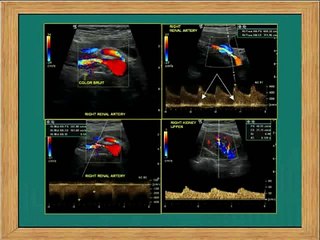

Renal Arterial Stenting - Secondary Hypertension - Live Case Part 2 - RHC Berlin 2014

Renal Arterial Stenting - Secondary Hypertension - Live Case - RHC Berlin 2014 For educational purposes only . If you are interested in the other RHC Talks .\rbr\rbrRenal Arterial Stenting - Secondary Hypertension - Live Case - RHC Berlin 2014 For educational purposes only . If you are interested in the other RHC Talks .

User: Renal Artery Stenosis